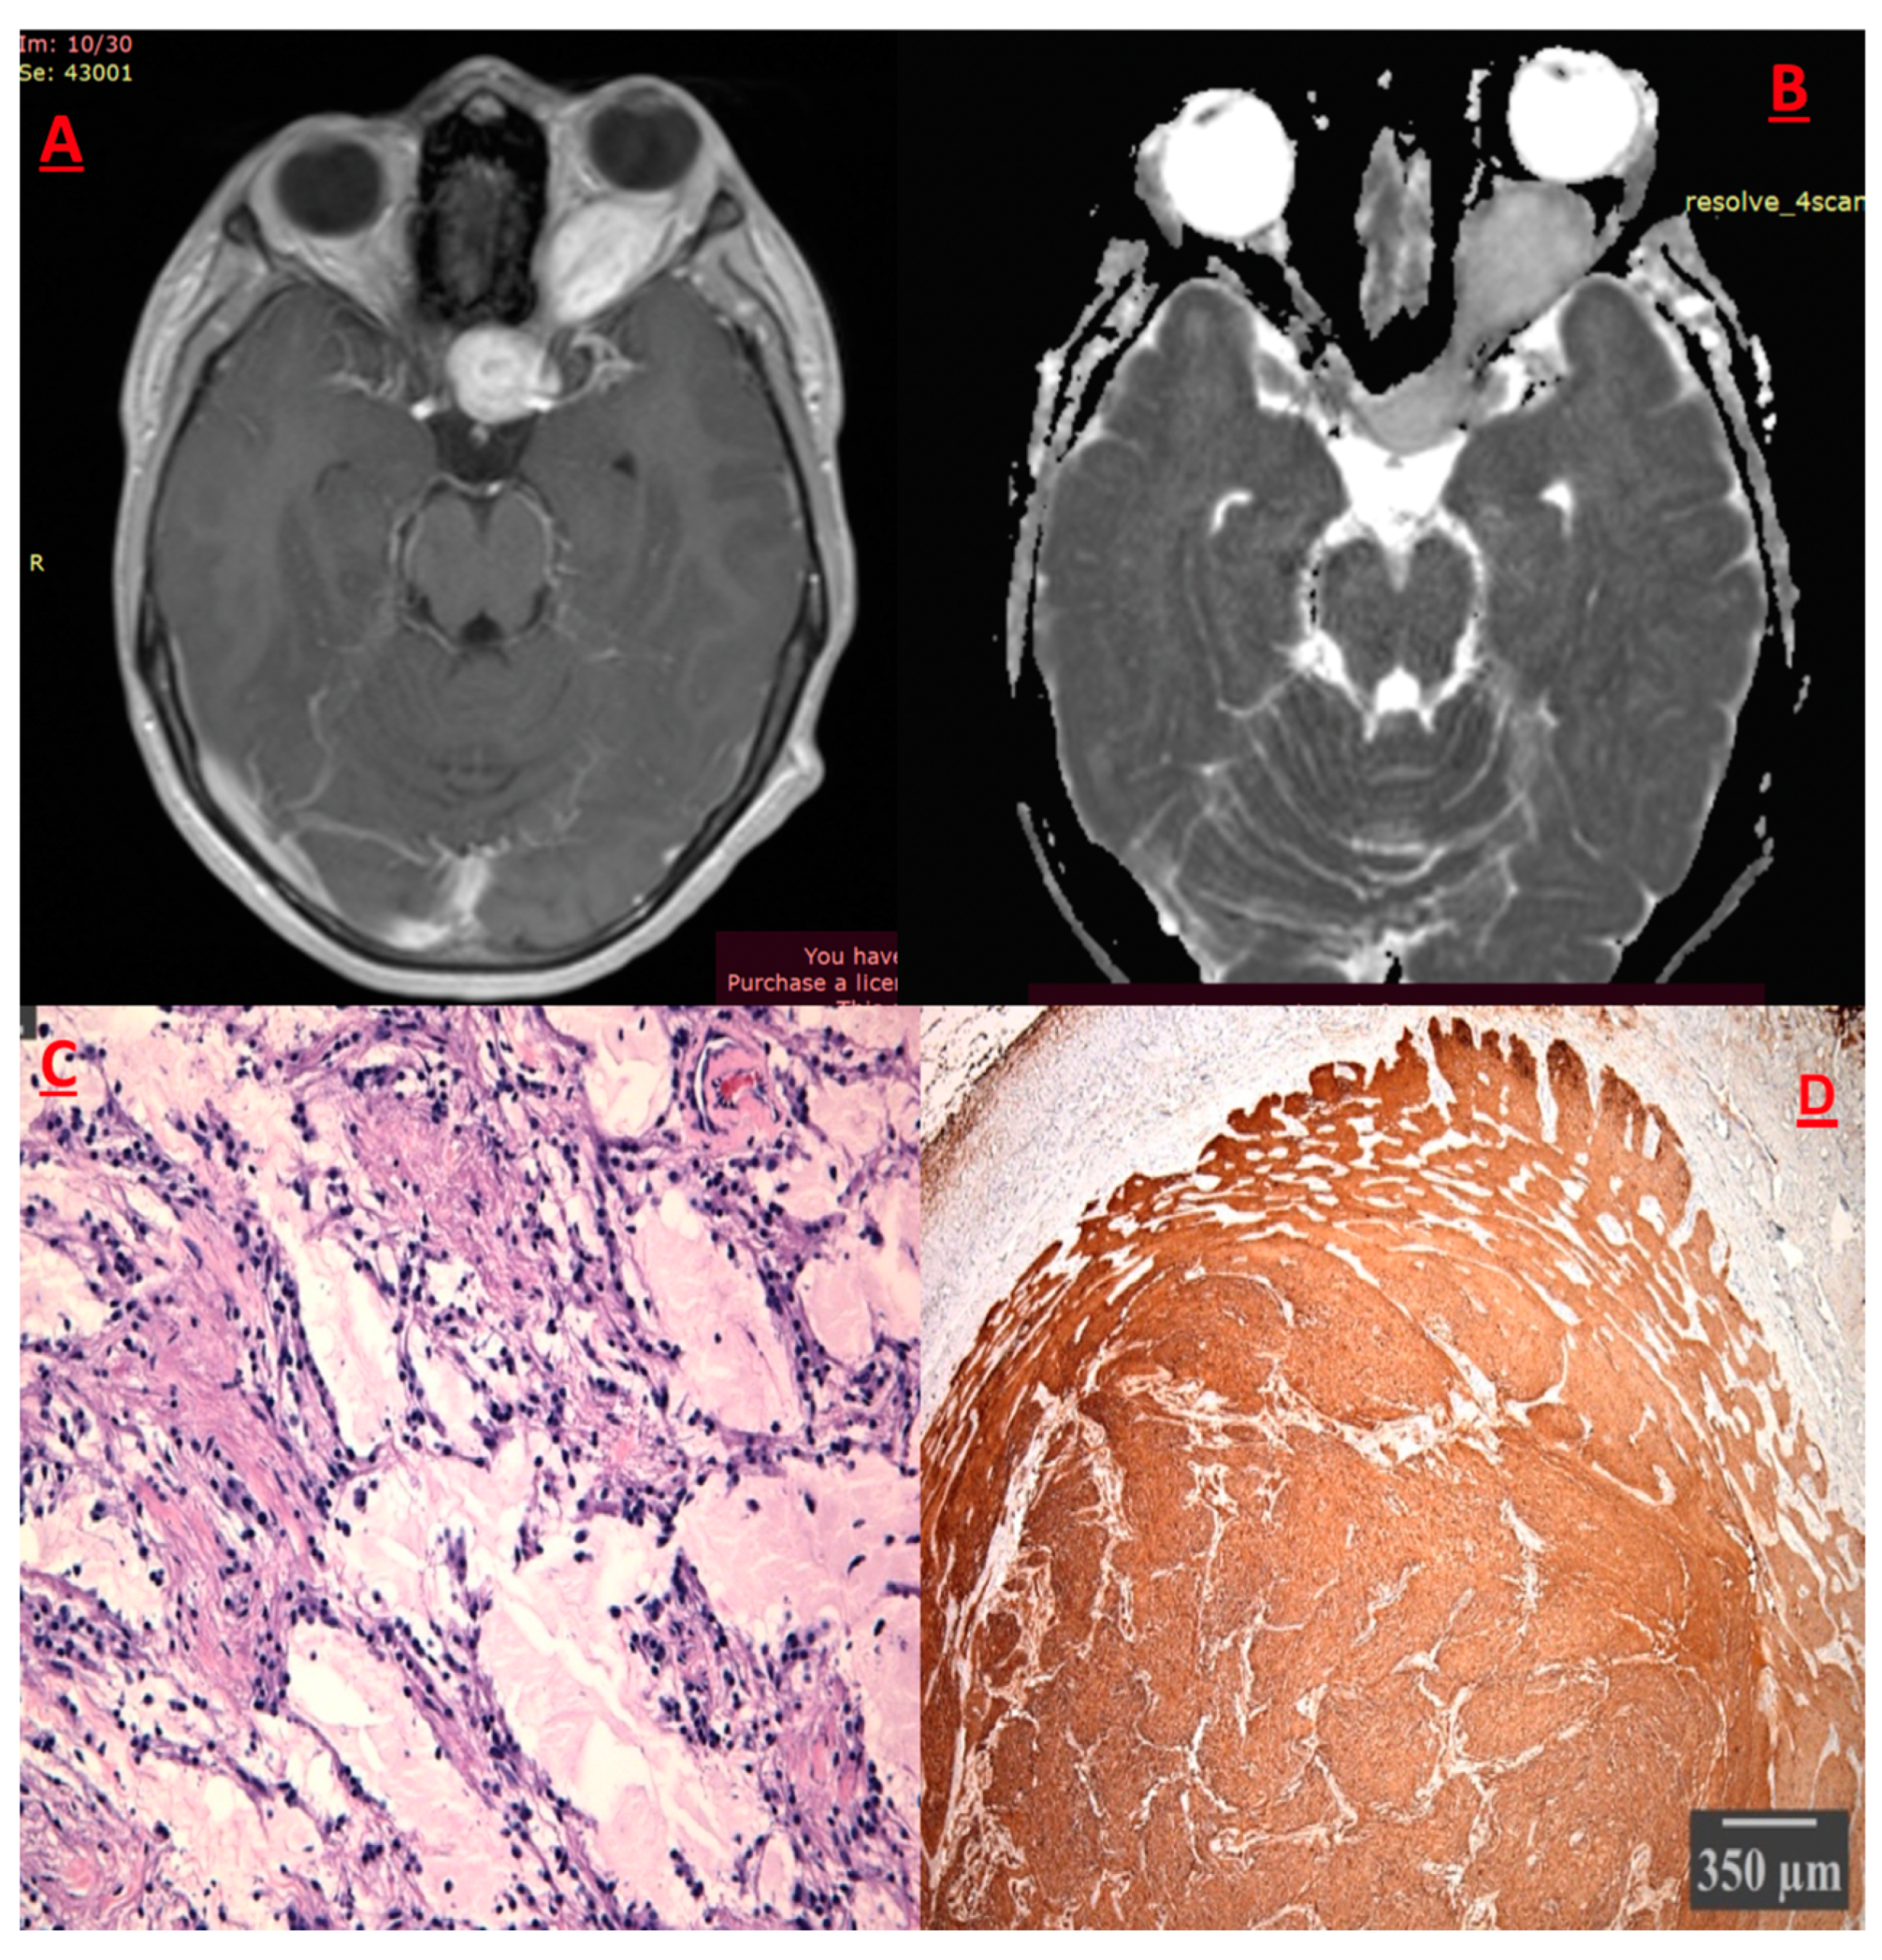

Pilocytic Astrocytoma (PA) (Figure 5)

Pleiomorphic Xanthoastrocytoma (PXA)